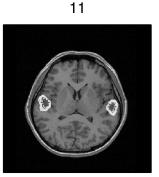

In the first experiment we place two dipoles at the level of primary hearing cortex.  In Figure 1 the right panel shows the location of the dipoles within the wire mesh of the head.  We perform a forward simulation and add 0.25% Gaussian random noise to the solution and then use our method to compute the inverse. Figure 2 displays the evolution of the solution during reweighted iterations. The maximum of the solution shifts, so, unlike the FOCUSS method [1] our minimum support method does more than accentuate the previous iteration’s peaks [6].

Figure 2.  Isolines of solution intensity superimposed on the corresponding MRI slice. Panels show solutions at iterations 1,2,3, and 11, numbered accordingly.